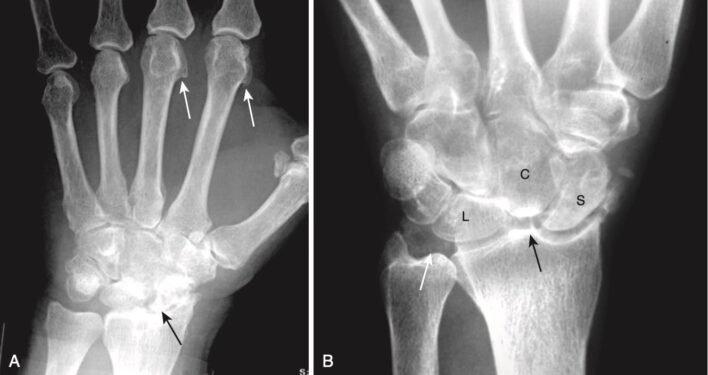

- Bệnh khớp pyrophosphate có thể không thể phân biệt được với bệnh thoái hóa khớp nguyên phát nhưng có một số điểm khác biệt quan trọng (Hình 12):

- CPPD có thể liên quan đến các khớp thường không bị ảnh hưởng bởi thoái hoá khớp, chẳng hạn như khớp bánh chè- đùi ở gối, khớp cổ tay- quay, khớp bàn – ngón (MCP) của bàn tay và các khớp ở cổ tay.

- Vôi hoá sụn khớp thường gặp trong bệnh khớp Pyrophosphate nhưng không cần thiết để chẩn đoán.

- Các nang (khuyết) dưới sụn thường gặp hơn, lớn hơn, nhiều hơn và lan rộng hơn so với thoái hoá khớp nguyên phát.

- Lồi xương dạng móc câu (hook-shaped bony excrescences) dọc theo đầu xương bàn đốt ngón 2 và 3 là một dấu hiệu thường gặp (xem Hình 12, A).

- Ở cổ tay, các dấu hiệu đặc trưng của CPPD bao gồm vôi hóa sụn sợi tam giác, hẹp khe khớp quay -cổ tay, tách xa xương thuyền và nguyệt hơn 3 mm (scapholunate dissociation, phân ly thuyền – nguyệt), và xẹp hàng dưới xương cổ tay về phía bên quay (scapholunate advanced collapse, sụp nặng khớp thuyền nguyệt) (xem Hình 12, B).

Hình 12. Bệnh lắng đọng calci pyrophosphate. A, Lồi xương hình móc câu dọc theo đầu xương bàn ngón thứ 2 và thứ 3 (mũi tên trắng); Hẹp khớp quay – cổ tay (mũi tên đen). B, Ở cổ tay, những phát hiện đặc trưng gồm sự vôi hóa sụn sợi tam giác (mũi tên trắng), sự phân ly của xương thuyền (S, scaphoid) và xương nguyệt (L, lunate), và sự sụp của xương cả (C, capitate) về phía xương quay (mũi tên đen), được gọi là sụp nặng thuyền – nguyệt, SLAC).